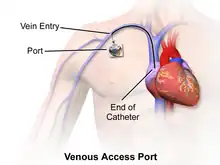

Catheter placement

- Central venous catheter placement: Vascular access and management of intravenous devices (IVs), including both tunneled and non-tunneled catheters (e.g., PIC, Hickman, port catheters, hemodialysis catheters, translumbar and transhepatic venous lines).

Central venous access refers to a variety of intravenous catheters placed in patients requiring certain long-term medications. These are much smaller in diameter than dialysis lines, but are larger and longer than a standard intravenous line (IV.) Examples include Hickman catheters, peripherally inserted central cathethers (or PICCs), tunneled small bore central venous catheters, and mediports. These lines differ in where they are inserted but are all placed under imaging guidance and adjusted so the end of the catheter sits in the vena cava adjacent to the heart. These catheters are designed to deliver strong medications, such as chemotherapy or prolonged courses of antibiotics, which are either dosed too frequently to keep placing new IVs or are too irritating to small veins be injected through a standard IV.